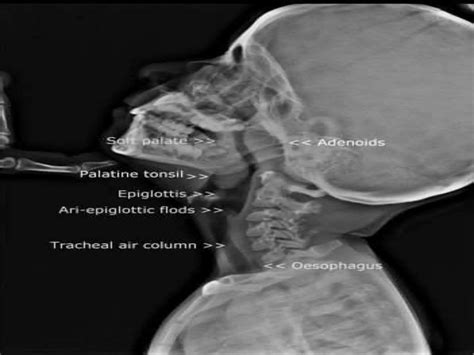

The adenoids are a mass of lymphoid tissue situated in the nasopharynx, the upper part of the throat behind the nose. They are part of the body's first line of defense against infections, particularly in the respiratory tract. Adenoids work by trapping and filtering out bacteria and viruses, helping to prevent infections from spreading further into the body.

• Imaging Tests: X-rays or CT scans may be ordered to assess the size and condition of the adenoids.